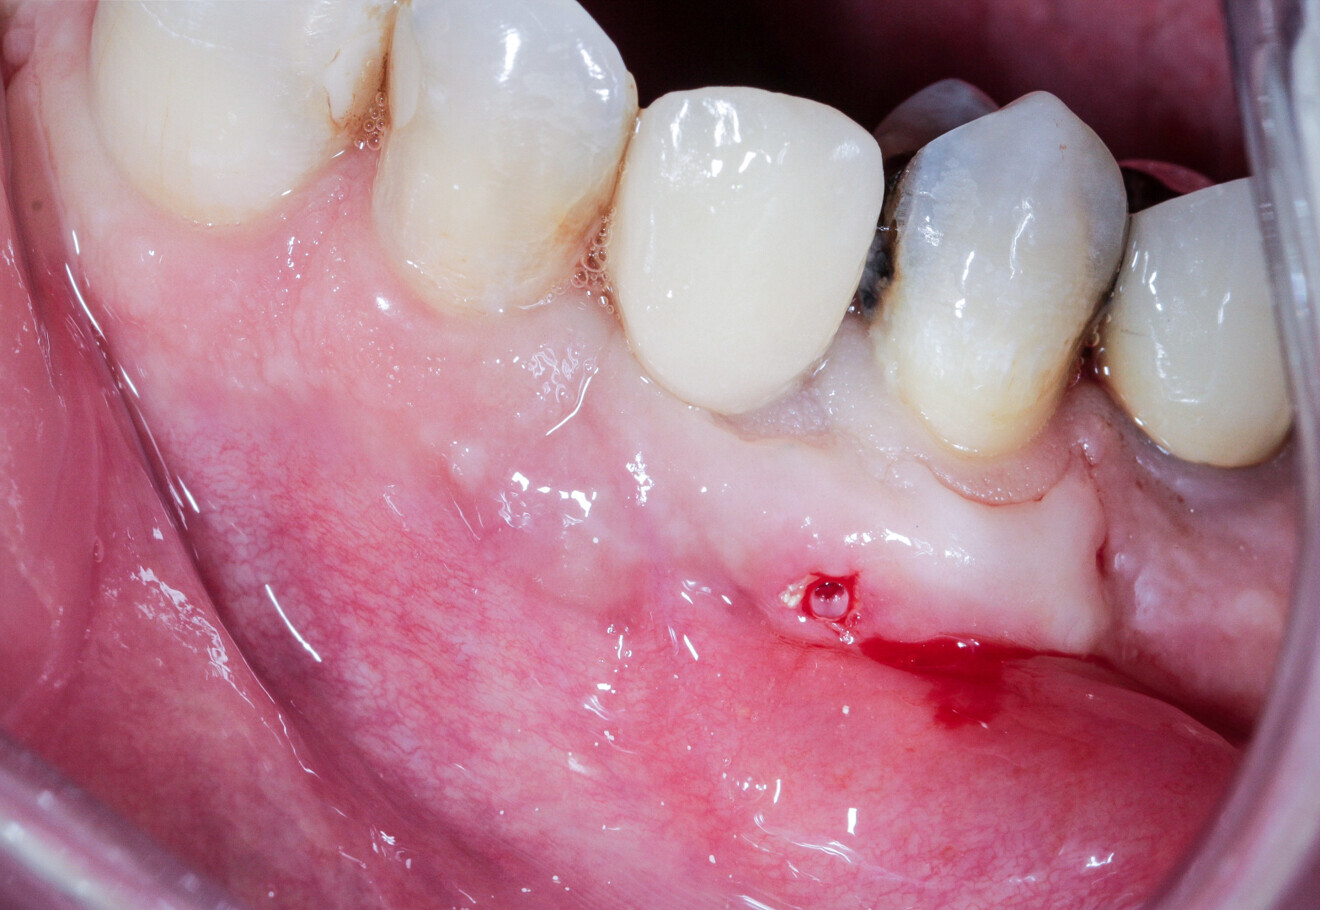

15: Radicular fracture at tooth #13 under a crown and with a fistula opposite.

A 55-year-old patient with a radicular fracture at tooth #13 under a crown and a fistula opposite was treated (Fig. 15). The plan was to treat this patient with simultaneous extraction, implantation and aesthetic restoration. Unfortunately, as sometimes happens and despite the precautions taken, a large part of the vestibular wall of the alveolus was extracted with the root, creating a significant bone defect. A full-thickness flap was elevated and the implant placed. The root was prepared and fixated with an osteosynthesis screw to replace the lost wall (Fig. 16). The space between the root and the implant was filled with a hydroxyapatite-based biomaterial (Fig. 17). This bone reconstruction was combined with a connective graft. The flap was stretched and sutured with a #5/0 resorbable braided thread (Fig. 18). An impression was taken and a temporary screw-retained prosthesis was made during the day by the laboratory and fitted the same evening. The sutures were removed on the tenth day. The temporary prosthesis was removed after two months to check that the implant had been successfully integrated into the bone. The osteosynthesis screw was visible under the gingiva and was removed after six months (Figs. 19 & 20). A CBCT assessment was performed at the same time. The radicular graft had ankylosed perfectly and the ridge regenerated ad integrum. The definitive prosthesis was fitted by our colleague (Fig. 21).